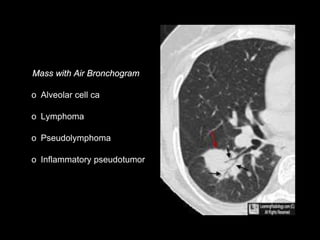

o Alveolar cell ca

o Lymphoma

o Pseudolymphoma

o Inflammatory pseudotumor